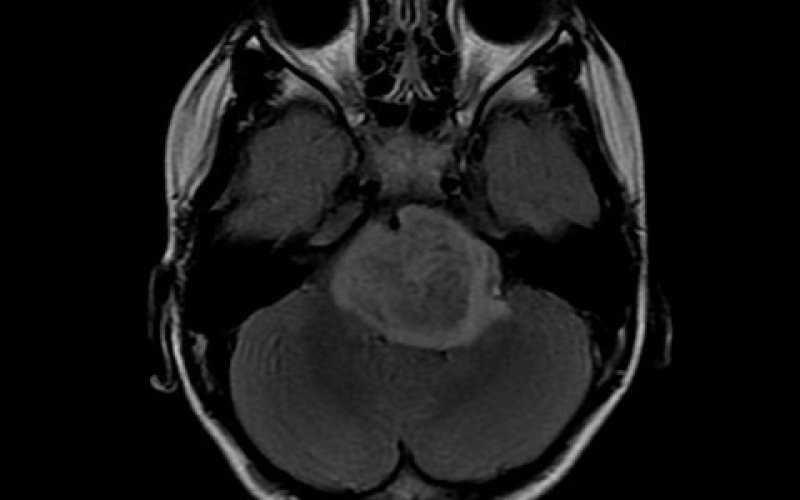

研究人员制定了一项新的计划,针对一组致命的儿童期致命性脑癌,这些癌症统称为弥漫性中线神经胶质瘤(DMG),包括弥漫性桥脑神经胶质瘤(DIPG),丘脑神经胶质瘤和脊髓神经胶质瘤。科学家们确定了一种药物对,它们可以共同杀死癌细胞并抵抗导致疾病的基因突变的影响。

DMG是具有侵略性且难以治疗的肿瘤,是美国儿童脑癌相关死亡的主要原因。DMG通常每年会影响数百名4至12岁的儿童。大多数儿童在诊断后一年内死亡。DMG的大多数情况是由组蛋白基因的特定突变引起的。组蛋白是细胞核中的蛋白质复合物。DNA包裹组蛋白形成染色质,将染色质包裹在细胞核中。DNA在组蛋白周围的缠绕和展开方式受酶(包括组蛋白脱乙酰基酶)的影响。这些酶添加或去除化学标签,从而间接控制基因是打开还是关闭。

尽管从这些筛查中获得了多种令人鼓舞的结果,但该团队专注于组蛋白脱乙酰基酶控制剂(如panobinostat)与称为蛋白酶体控制剂(如marizomib)的药物的组合。蛋白酶体控制剂会阻止细胞正常的蛋白质回收过程。panobinostat-marizomib组合在几种模型中对DIPG细胞具有高毒性,包括代表该疾病主要遗传亚型的DIPG肿瘤细胞培养物和从患者肿瘤移植的细胞的小鼠。这种组合还可以减少小鼠的肿瘤大小并增加其存活率。在从患者细胞培养物中生长的细胞中发育的脊髓和丘脑DMG模型中发现了类似的反应。